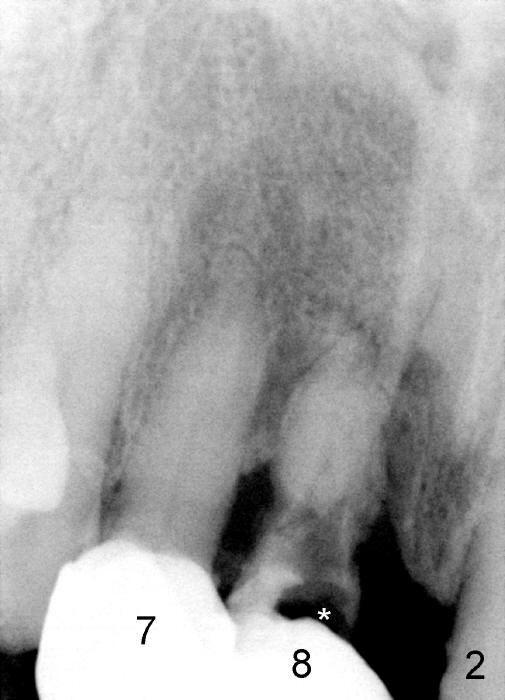

A 64-year-old lady requests replacing #7 and 8 crowns (Fig.1,2). When #8 is extracted, the labial plate is found to be missing (Fig.3). Following 2 mm pilot drill (Fig.4,5 P), 3.8 mm tap drill (Fig.6,7 T) and 4.5x14 mm implant (Fig.8 I) and 4.8 mm abutment (Fig.9 A), corticocancellous bone is harvested from the left tuberosity and placed in the labial gap of the socket (Fig.10 G). Collagen dressing is placed over the bone graft (Fig.11 C). The former is secured in place by an immediate provisional (P).

Four-month follow up shows that bone graft from the tuberosity appears to have healed with the implant microthreads (Fig.17 *); there is a diastema between #8 and 9 (arrowheads). Before removal of the provisionals of #7 and 8 for final impression, new composite is added to the mesial surface of #9 as the first step of closure of the diastema (Fig.18 <).